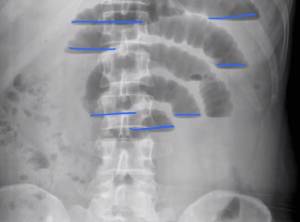

Для окончательного подтверждения диагноза «кишечная непроходимость» применяются инструментальные методы исследования. К ним относятся:

- Рентгенологическое исследование — это основной и наиболее распространенный метод, который используется при подозрении на кишечную непроходимость. Наличие данного состояния может быть подтверждено несколькими признаками: кишечными арками, чашами Клойбера и перистальтикой кишечника.